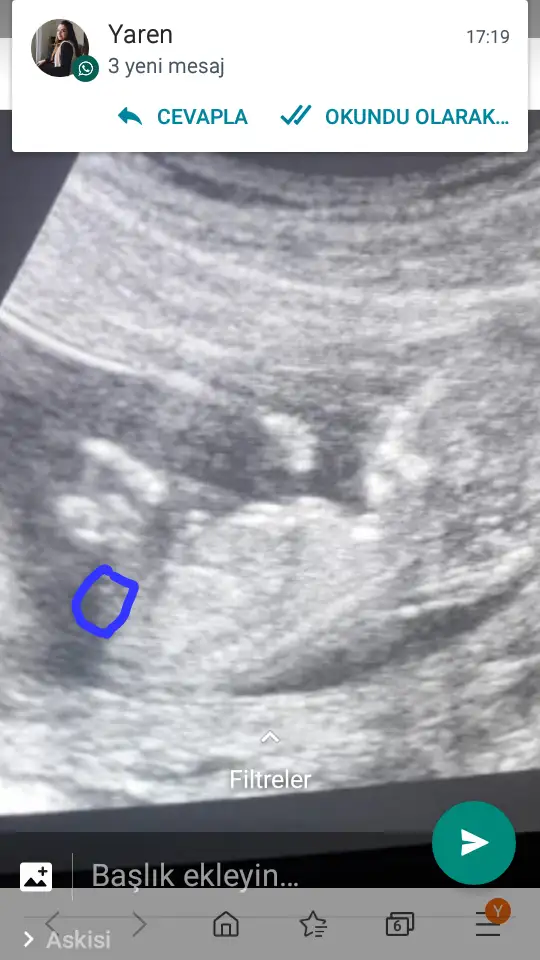

Başka usg varmı çok net değil diklik görünüyor sanki erkek gibi emin olamıyorum12 haftalık acaba cinsiyet tahmininde bulunabilir misiniz

Başka usg varmı çok net değil diklik görünüyor sanki erkek gibi emin olamıyorum

Yaa yukardan arkadaş bana mesaj yazıyorduYani şu gördüğüm nub ise dik görünüyor bacaklar yukarda nubunu değiştirmiyorsa pozisyon erkek gibiEki Görüntüle 2584968